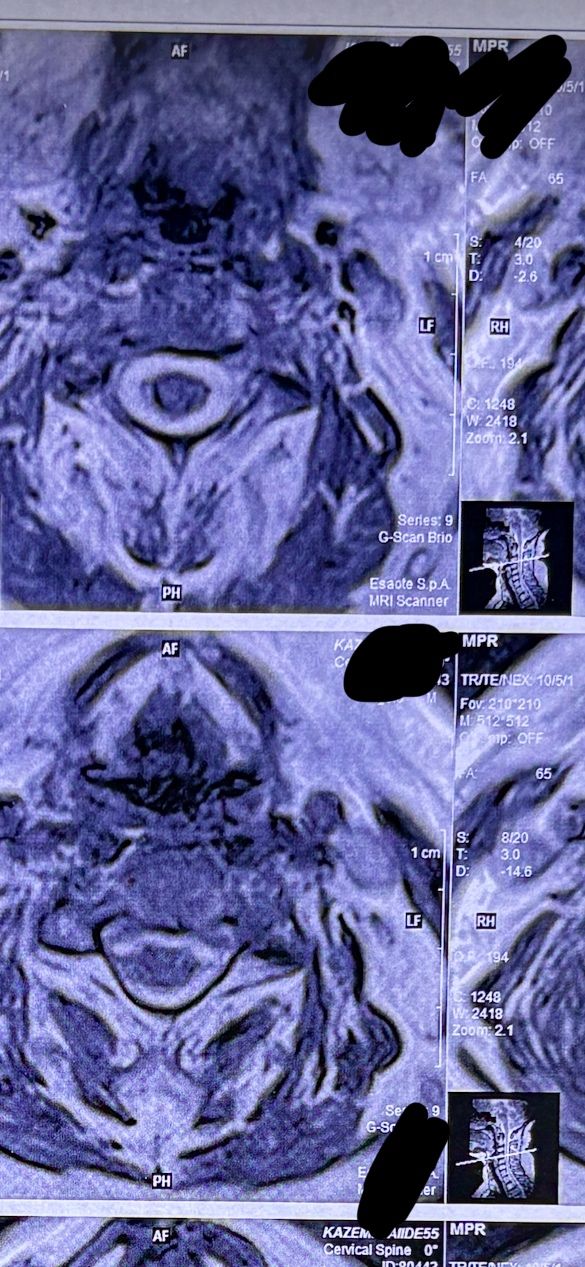

41 years old man presented to my clinic in October 2023 with acute and sever R neck pain with radicular pain to his R upper extremity along C6 dematom since 2 weeks ago. Examination didn’t show any upper motor signs. Was suggested urgent surgery

I ordered EMG/ NCV : showed mild R C6, C7 irritation without any active axonal loss

In his MRI was reported R. para R. IVF Massive extrusion. I decided to control his pain and manage this patient with reevaluation of patient every other session. For 5 sessions i just used acupuncture and laser and IFC and mild adjustments to his R. T3-T7 and mild arthosteem to above and below involved segment. Cervical adjustment considered contraindicated for this patient. From session 6th- 8th i started to use mild/gentle cervical decompression. He used soft cervical collar all the time. His pain decreased by 80 percent

I gave him cervical traction pump to be used 3-5 times per day at home for the next 3 months and i released the patient. He was evaluated every week once for one month and after that every 2 weeks. After 3 month I repeated MRI. Size of the herniated disc was reduced greater than 50 percent. Asked him to do another mri in 6 months

MRIs before and after proper management of this patient: